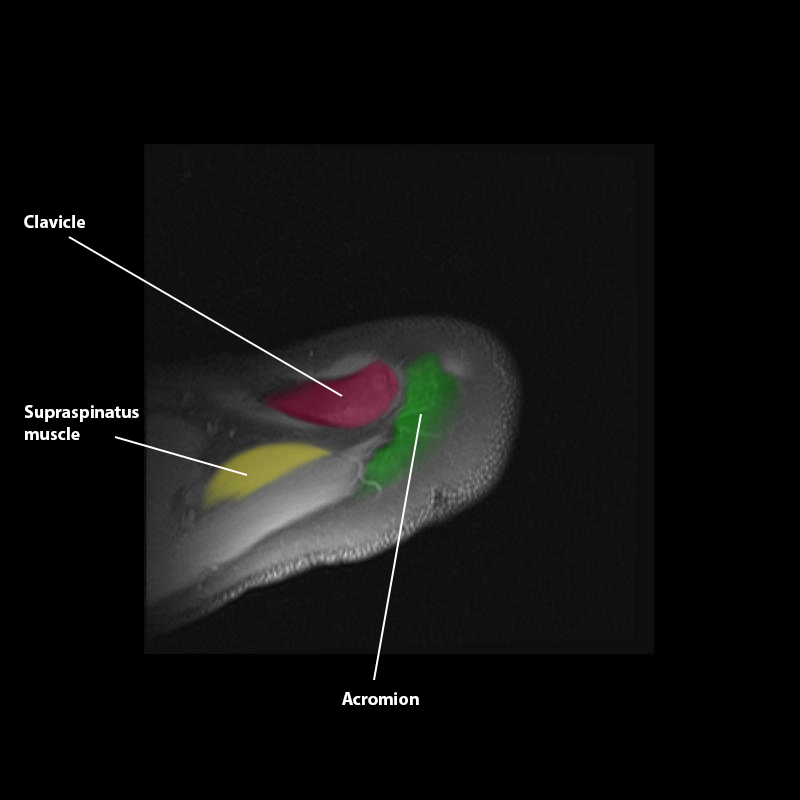

Shoulder MRI Anatomy